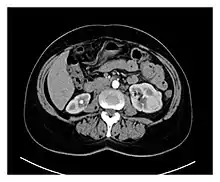

Preoperative contrasted CT scans of the patient, showing multiple bilateral kidney tumors, with diameters ranging between 1 and 5 cm. Radiologically, most of the tumors have malignant characteristics due to their hypervascularity and radiopaque enhancement.